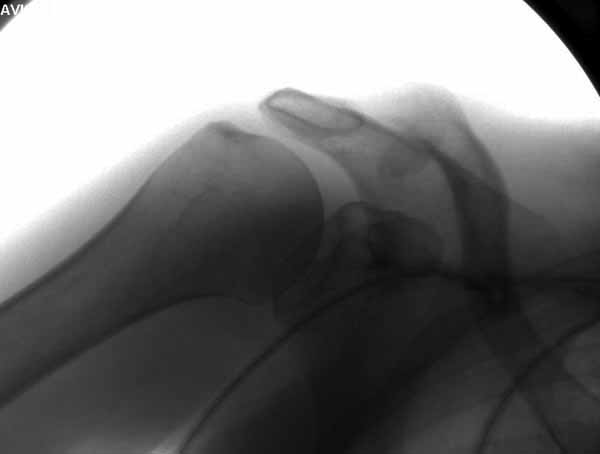

Из заданного вопроса в этом посте я понял, что разговор идет по поводу “методики применения ключичной пластины с крючком при акромиальных переломах”, т.е не ведется разговор “по поводу лечения косых переломов ключицы”.

Если так, тогда Юрий прав, методов лечения акромиона пластинами нельзя было найти. Обычно изобретали из реконструкционных пластин 2.7 или 2.4 мм толщиной. Такая фиксация адекватно удерживает перелом акромиона. Только недавно компания Acumed создала пластину для переломов акромиона, здесь линк: http://www.acumed.net/sites/default/files/literature/brochure-surgical-technique/CPS00-11-A.pdf.

По поводу пластины с крючком, Ваше заключение "не вижу препятствий для фиксации акромиального косого перелома ключицы для МОС использовать пластинку с крючком" вызывает сомнение.

Предназначенную для лечения повреждений связочного аппарата акромиально-ключичного сочленения пластину можно применить не при всех переломах акромиального конца ключицы. Потому что имплант рассчитан на интактную ключицу и не для переломов ключицы. Пластина короткая, не покрывает медиальный диафизарный фрагмент ключицы и за счет тракции стерноклеидомастоидеус такая фиксация прорвется через несколько дней.

Имя     : 2 Clavicle AC introp 1.jpg